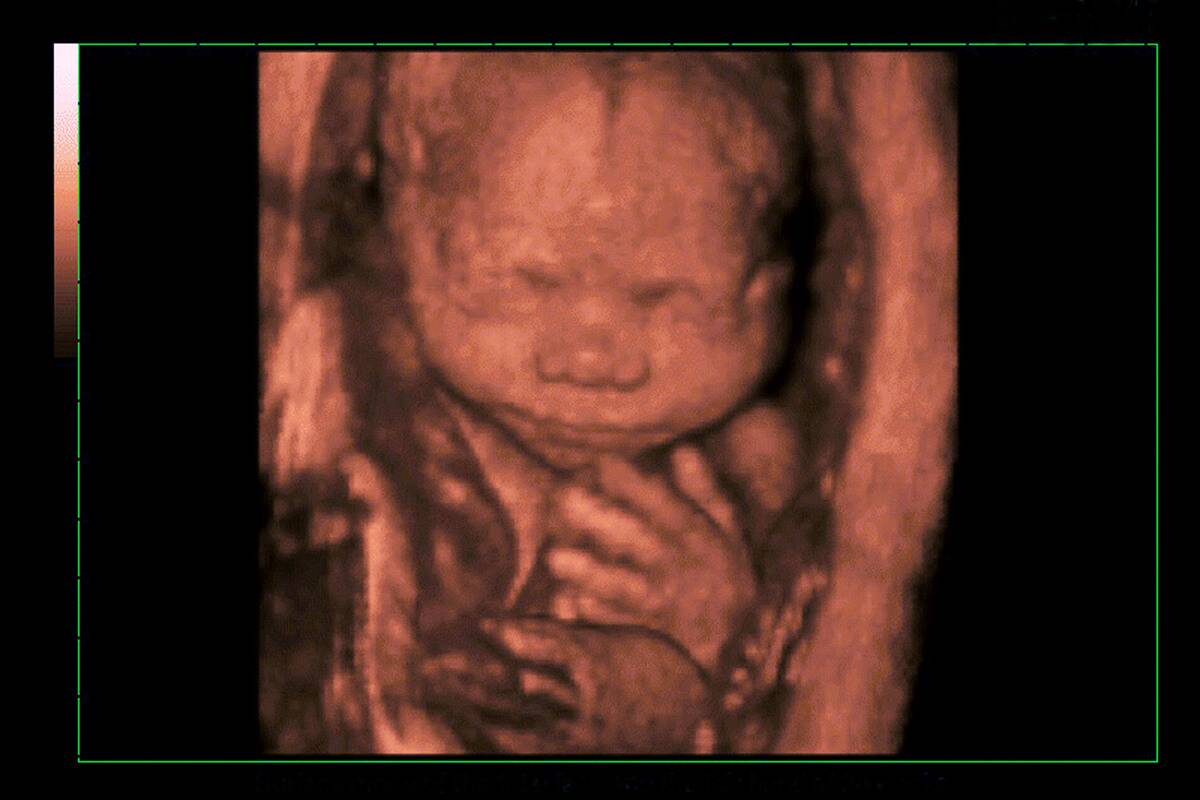

The Way of the Future: 3D Prenatal Ultrasounds

If you have money to spare you can ditch the traditional ultrasound picture you have hanging on your fridge and get a 3D prenatal ultrasound instead.

With this pricier method, an MRI scan is done of the mother’s womb through 3D imaging software. You can even take it up a step and opt for a 4D ultrasound. This uses the same technology as with 3D but has the added element of motion.